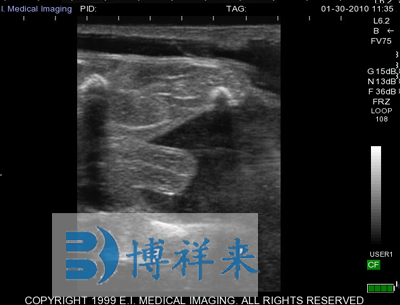

| 适应条件 | 防水、防尘、防摔击 | 显示模式 | B模式,B+M模式(B模式下M线可以调节) |

| 超声类型 | 数字超声 | 产科软件 | 各种动物妊娠期参数表格 |